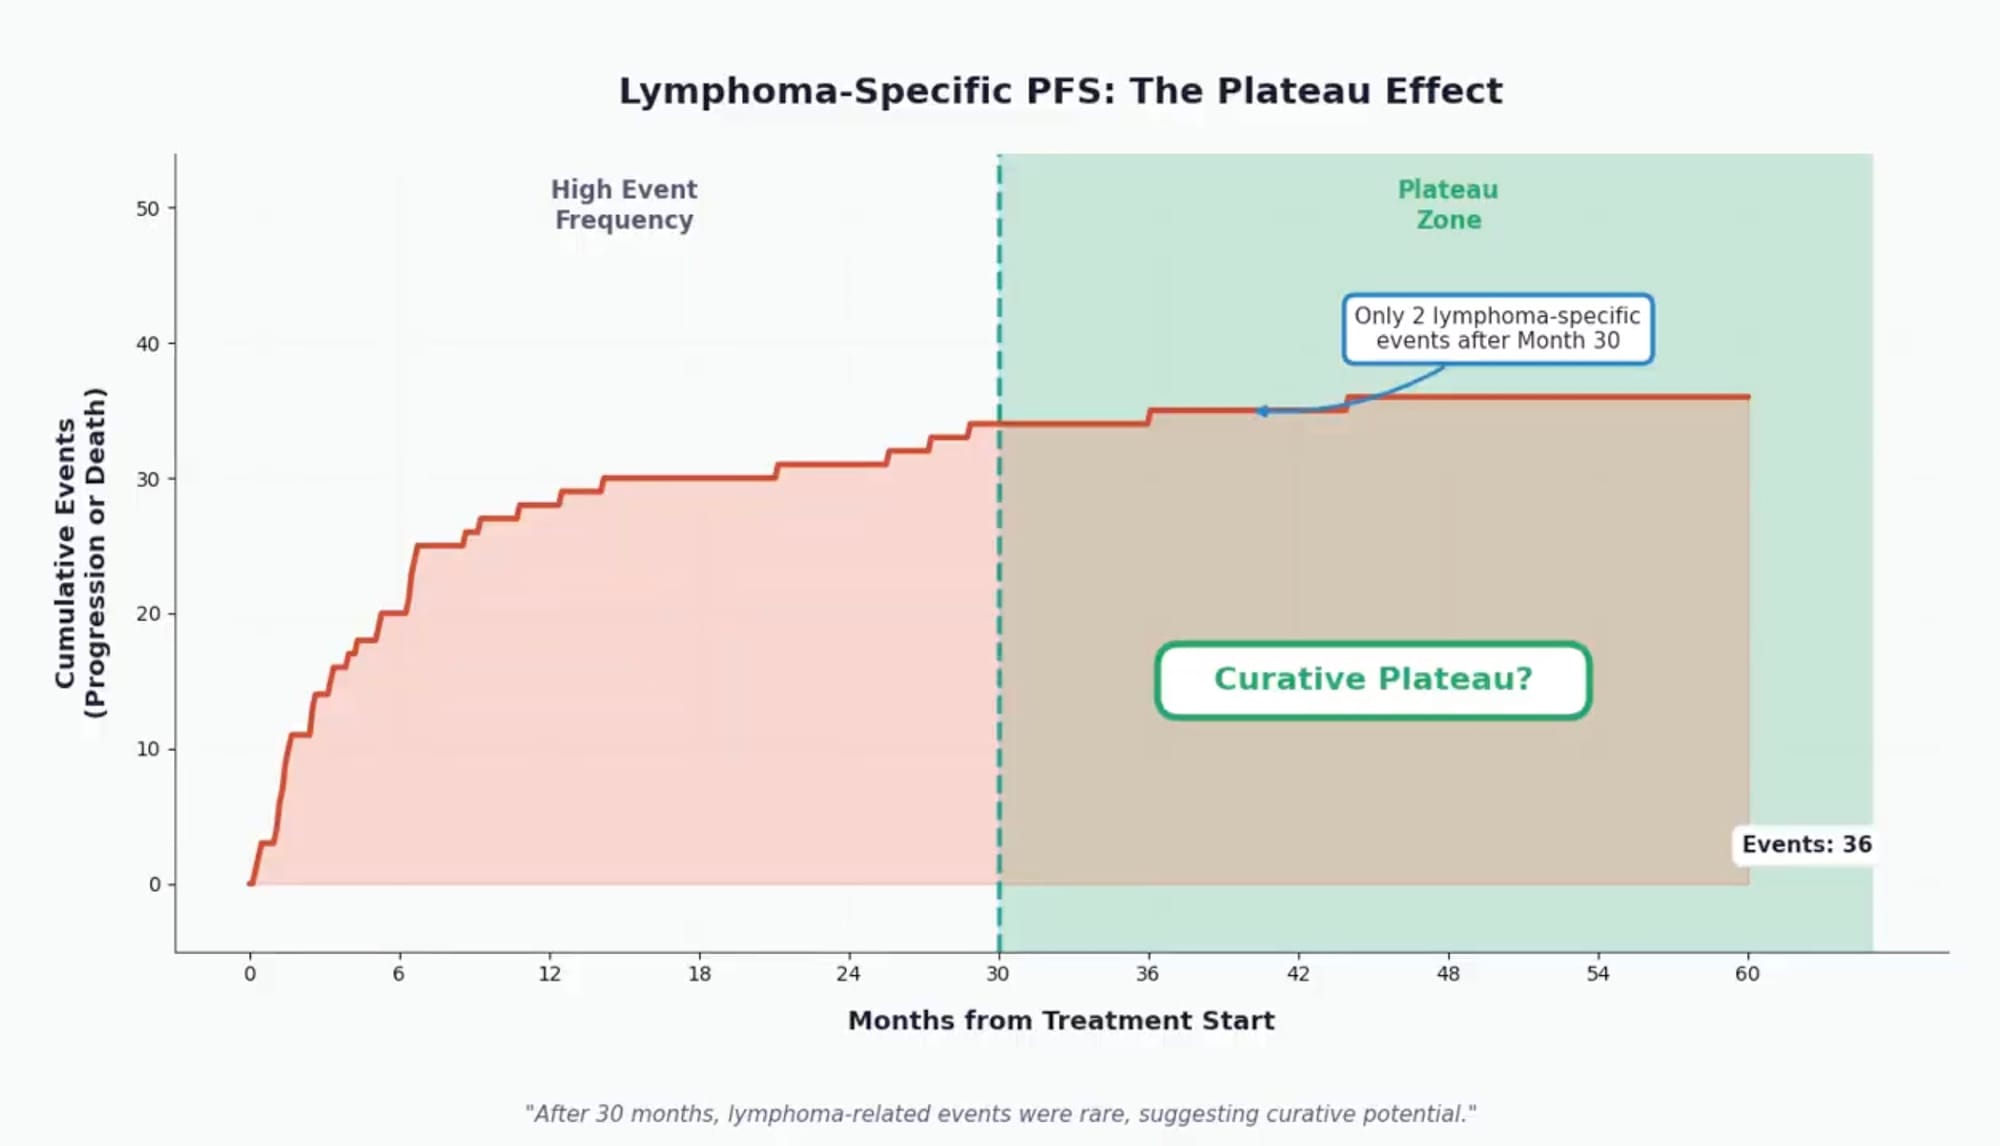

A plateau in lymphoma-specific outcomes: The investigators observed that after 30 months post-infusion, progression or lymphoma-related deaths became rare—only two such events occurred beyond this timepoint. This plateau suggests that patients who remain in remission at 2.5 years have a high likelihood of sustained disease control, a pattern consistent with potential curative benefit for a subset of patients.

The plateau phenomenon: Unlike in diffuse large B-cell lymphoma where a clear survival plateau emerges around two years post-CAR T, the pattern in follicular lymphoma is more gradual—partly because of the longer latency before progression events manifest clinically and competing risks of death from other causes. Lymphoma-specific progression-free survival may more accurately capture the curative potential in this disease.

For a disease historically characterized by repeated remissions and relapses, the emergence of a plateau in lymphoma-specific outcomes—with rare events beyond 30 months—suggests that for a substantial proportion of patients, a single CAR T-cell infusion may provide lasting disease control.